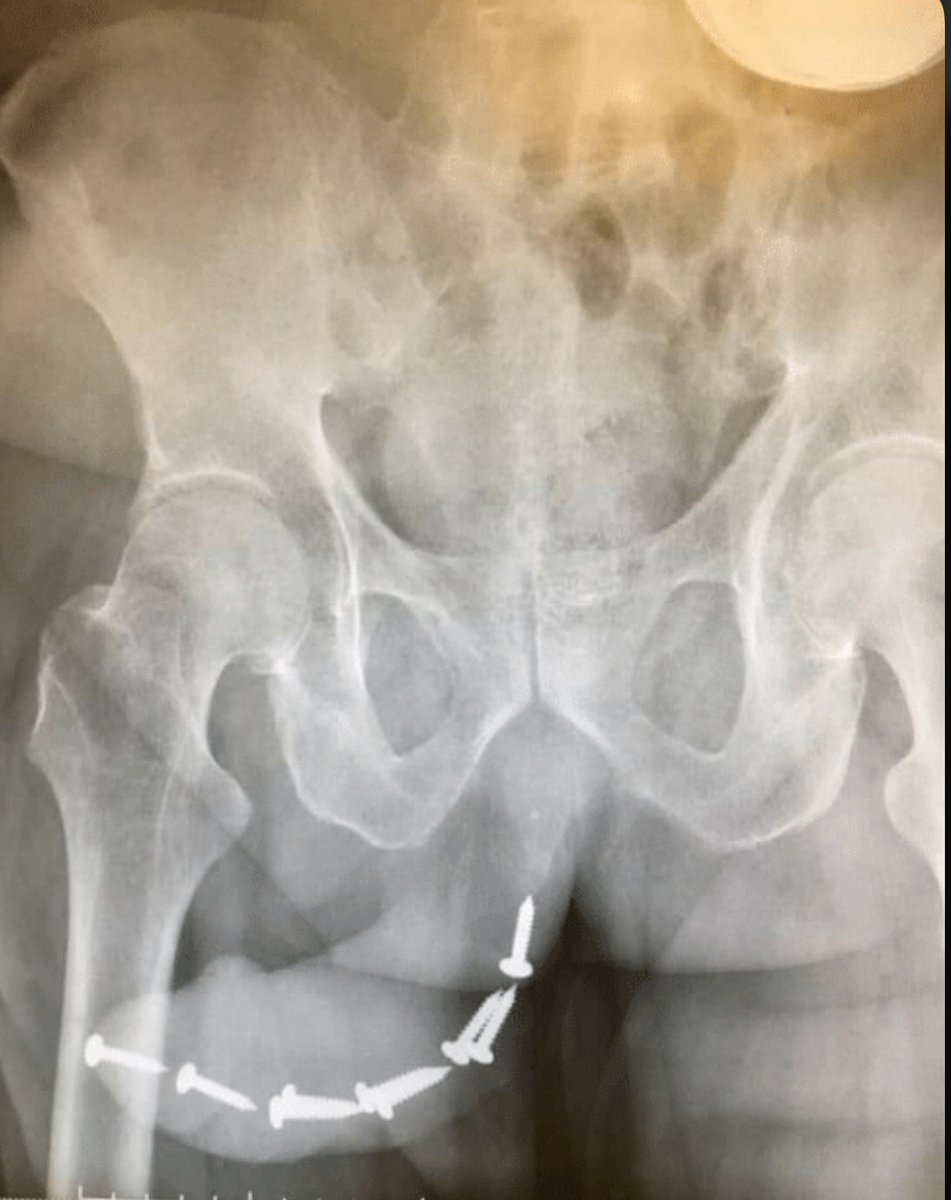

@ArunkumarDr

Ascending Screwthrogram

@DrLongissimus

Screwed around found out